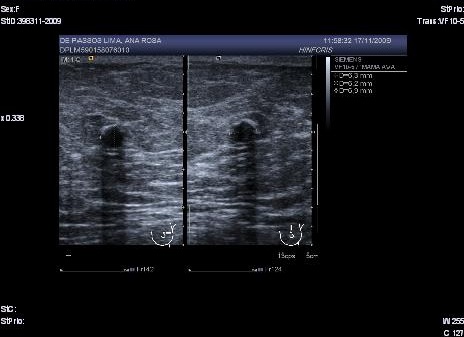

In a mammography of April 2009, a subareolar, oval-shaped, well-defined nodule of 16 mm with mammographic characteristics was observed: possibly benign (Birds 0). Extended studies were indicated through ecography of the left breast. The left breast ecography showed a well-defined cystic lesion in the left subareolar region with heterogeneous content, 19.1 x 12 x 17.8 mm that when compared with previous studies since 2006 showed an increase in size (Birads 4). The FNA evidenced a negative extension for malignant cells with findings consistent with the cystic content. With the above results ultrasound monitoring of the lesion after 3 months was decided upon. In the ultrasound of the left breast (July 2009) a cystic lesion was found with heterogeneous subareolar content of 12 x 8.4 x 12 mm (Fig. 1).